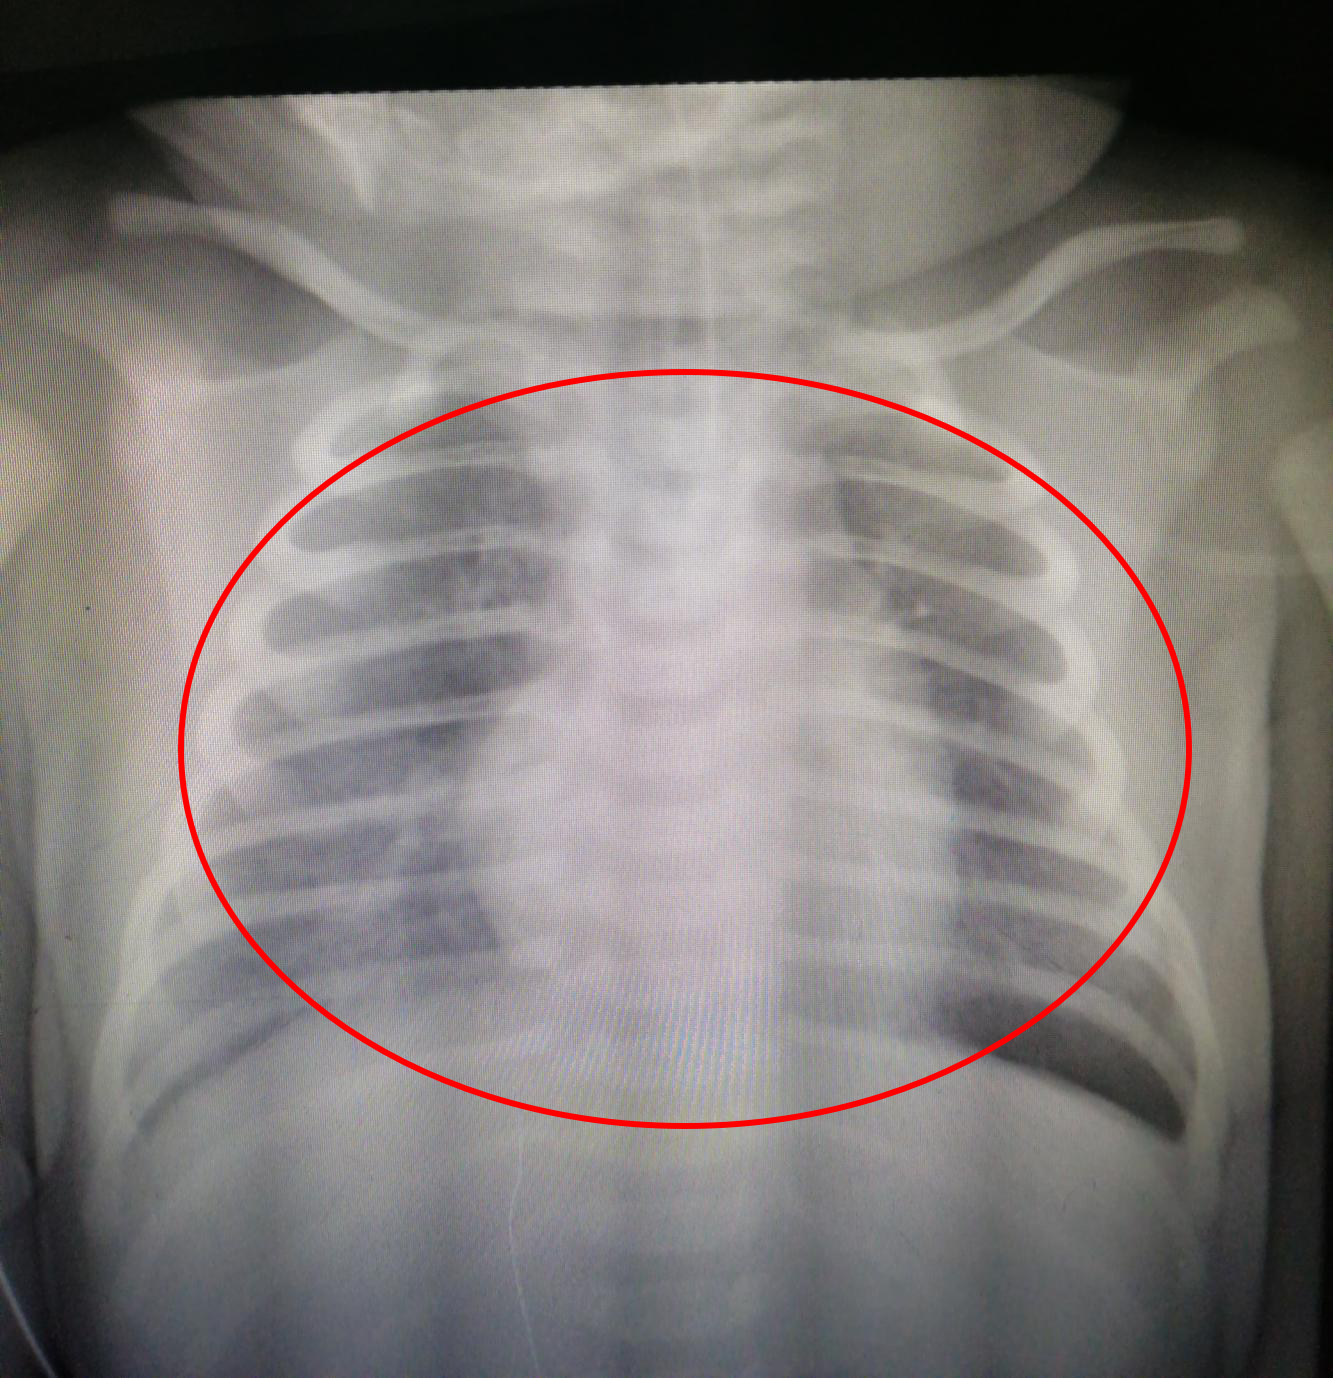

功夫不负有心人,在新生儿科医护人员精心治疗和护理下,安安病情明显好转。治疗第3天,安安的肺心影、肺膈影清晰可见,肺顺利通气,复查床旁心脏彩超,安安的肺动脉高压也降低了;治疗第7天,安安顺利撤除高频呼吸机;治疗第17天,安安病情治愈,顺利康复出院。

治疗第3天的胸部X线片:双肺和心脏、双肺和膈肌界线清晰可见